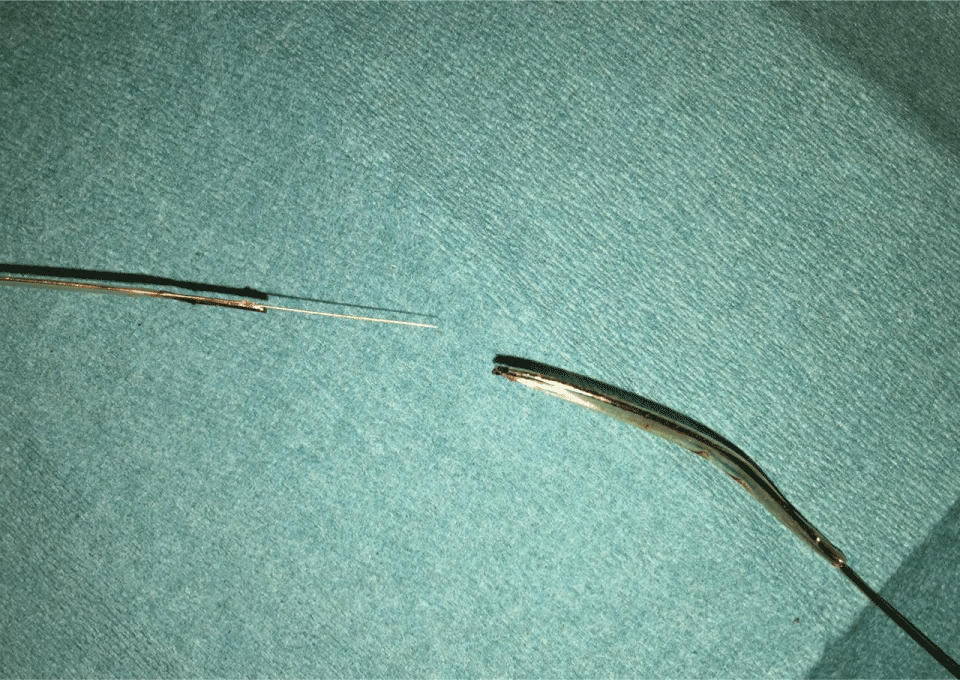

Figure 4: Ruptured balloon after successful removal. View Figure4

Figure 5: Closeup of the site of rupture and detachment. View Figure 5